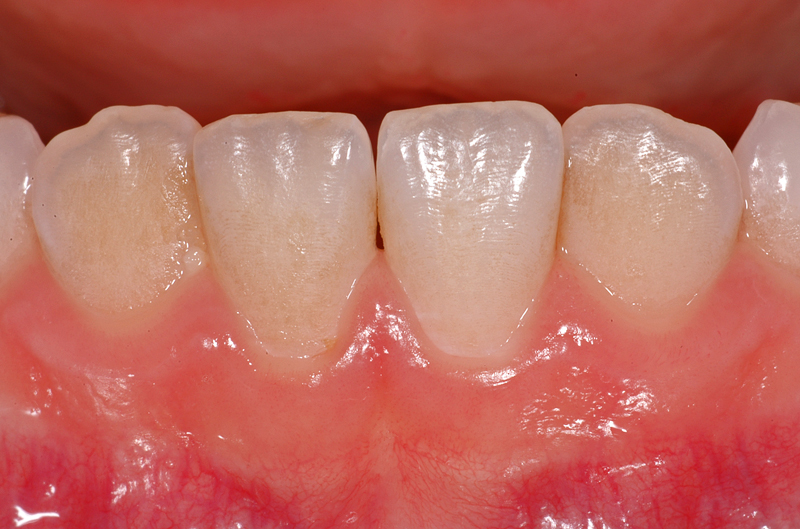

Und hier ein Fall mit leichten bräunlichen Verfärbungen auf den Aussenflächen der Unterkiefer-Schneidezähne, bedingt durch eine nicht optimale Mundhygiene.

In den Zahnzwischenräumen ist auch wenig Zahnstein vorhanden, er ist ebenfalls leicht bräunlich.

Diese Verfärbungen lassen sich gut mit einer professionellen Reinigung entfernen, danach sind die Zähne wieder sauber und «weisser».

- Bräunliche Verfärbungen auf Aussenflächen